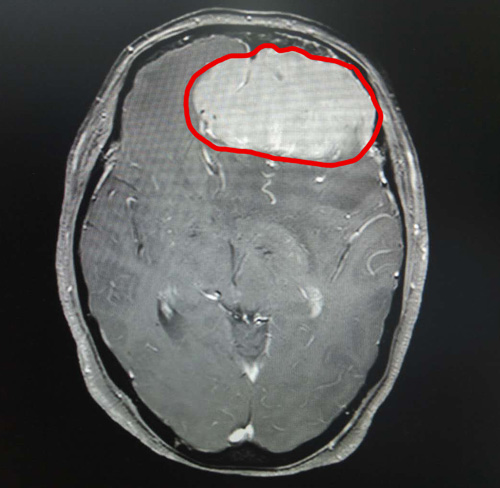

頭顱MRI增強(qiáng)顯示,丁阿姨的前顱窩有巨大的團(tuán)塊狀異常信號(hào)。腫瘤大小約為6.9×5.6×5.4厘米,其大小與鴨蛋接近。

頭顱MRI影像清晰顯示了巨大的腦膜瘤